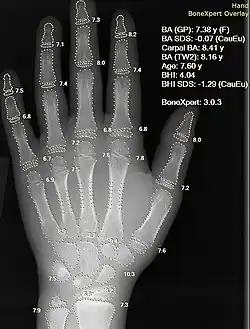

- Aplicação na área da saúde: a introdução na medicina com a criação da Inteligência artificial na Medicina (IAM) propôs a ajuda mútua entre profissionais da saúde e da computação com a ideia de realizarem uma revolução na área médica. A partir dos anos 70 e 80, grandes universidades americanas iniciaram projetos para auxiliar no processo de diagnósticos, como MIT, Tufts University, Universidade de Pittsburgh, entre outras. Esses programas rapidamente atraíram vários dos melhores cientistas da época, com os primeiros anos da realização dos projetos sendo até hoje referências na história da IAM, por terem sido extremamente ricos e produtivos.

- Diagnóstico: programas de diagnóstico médico baseados na analise probabilística foram capazes de executar tarefas no nível de um médico especialista em diversas áreas da medicina. Heckerman (1991) descreve um caso em que um importante especialista em patologia de gânglios linfáticos ridiculariza o diagnóstico de um programa em um caso especialmente difícil. Os criadores do programa sugeriram que ele pedisse ao computador uma explicação do diagnóstico. A máquina destacou os principais fatores que influenciaram sua decisão e explicou a interação sutil de vários sintomas nesse caso. Mais tarde, o especialista concordou com o programa.

Aplicações na promoção da saúde

A introdução de IA na área de saúde propôs a ajuda mútua entre profissionais da saúde e da computação com a ideia de realizarem uma revolução na área médica. A Organização Mundial de Saúde (OMS) divulgou diretrizes quanto ao uso ético dessa tecnologia. [75]O grande investidor em pesquisa em IA na saúde no mundo é a multinacional de tecnologia Alphabet, do grupo Google. O Instituto de Tecnologia de Massachusetts (MIT) e as universidades Stanford e Harvard, nos Estados Unidos, e as de Oxford e Cambridge, no Reino Unido, também se destacam. No Brasil, USP, Universidade Estadual de Campinas (Unicamp) e Universidade Federal de Minas Gerais (UFMG) estão entre as que mais se dedicam a esse campo de pesquisa.[76]

Utilização na área médica

A IA na área da saúde é frequentemente usada para classificação, seja para automatizar a avaliação inicial de uma tomografia computadorizada ou EKG ou para identificar pacientes de alto risco para a saúde da população. A amplitude de aplicações está aumentando rapidamente. Como exemplo, a IA está sendo aplicada ao problema de alto custo das questões de dosagem - onde as descobertas sugeriram que a IA poderia economizar US $ 16 bilhões. Em 2016, um estudo inovador na Califórnia descobriu que uma fórmula matemática desenvolvida com a ajuda de IA determinava corretamente a dose exata de medicamentos imunossupressores a serem administrados a pacientes com órgãos.[79]

Um estudo foi feito com transferência de aprendizagem, a máquina realizava um diagnóstico semelhante a um oftalmologista bem treinado, e podia gerar uma decisão em 30 segundos sobre se o paciente deveria ou não ser encaminhado para tratamento, com mais de 95% de acerto.[84]

As redes neurais artificiais são usadas como sistemas de apoio à decisão clínica para diagnóstico médico, como em tecnologia de processamento de conceito em software EMR.

- Interpretar imagens médicas auxiliada por computador. Esses sistemas ajudam a digitalizar imagens digitais, por exemplo, da tomografia computadorizada, para aspectos típicos e para destacar cortes conspícuos, como possíveis doenças. Uma aplicação típica é a detecção de tumores.